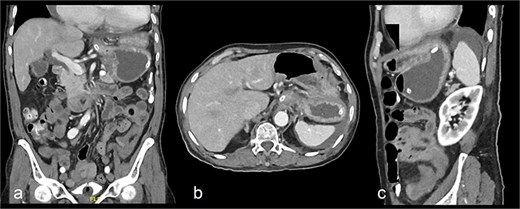

On presentation, the patient was fully oriented with vitals in the normal range. On examination, the abdomen was soft and not distended. There was a scar at the lower midline laparotomy for an unknown indication. There was no abdominal tenderness or any signs of peritonitis. All hernial orifices were intact. His laboratory results were unremarkable with a normal renal and electrolytes profile and no leukocytosis or anemia. Abdominal radiograph demonstrates multiple dilated loops of small bowel with prominent air-fluid levels. No evidence of free intraperitoneal air is identified to suggest perforation. No radiopaque foreign bodies or mass lesions are visible (Fig. 1). The patient underwent computed tomography (CT) of abdomen with IV contrast. The stomach demonstrates abnormal orientation with inferior displacement of the fundus and superior displacement of the gastric pylorus near the gastroesophageal junction, with gastric distension. Mild perigastric and perisplenic fluid. Preserved gastric wall enhancement. Mild pelvic fluid is noted (Fig. 2).

Contrast-enhanced CT abdomen and pelvis shows nasogastric (NG) tube noted in position. The stomach demonstrates abnormal orientation with inferior displacement of the fundus and superior displacement of the gastric pylorus near the gastroesophageal junction, with interval improvement of the gastric distension, likely mesenteroaxial gastric volvulus. Persistent mild perigastric and perisplenic fluid. Preserved gastric wall enhancement. Mild pelvic free fluid is noted. No free air or size significant lymph node.